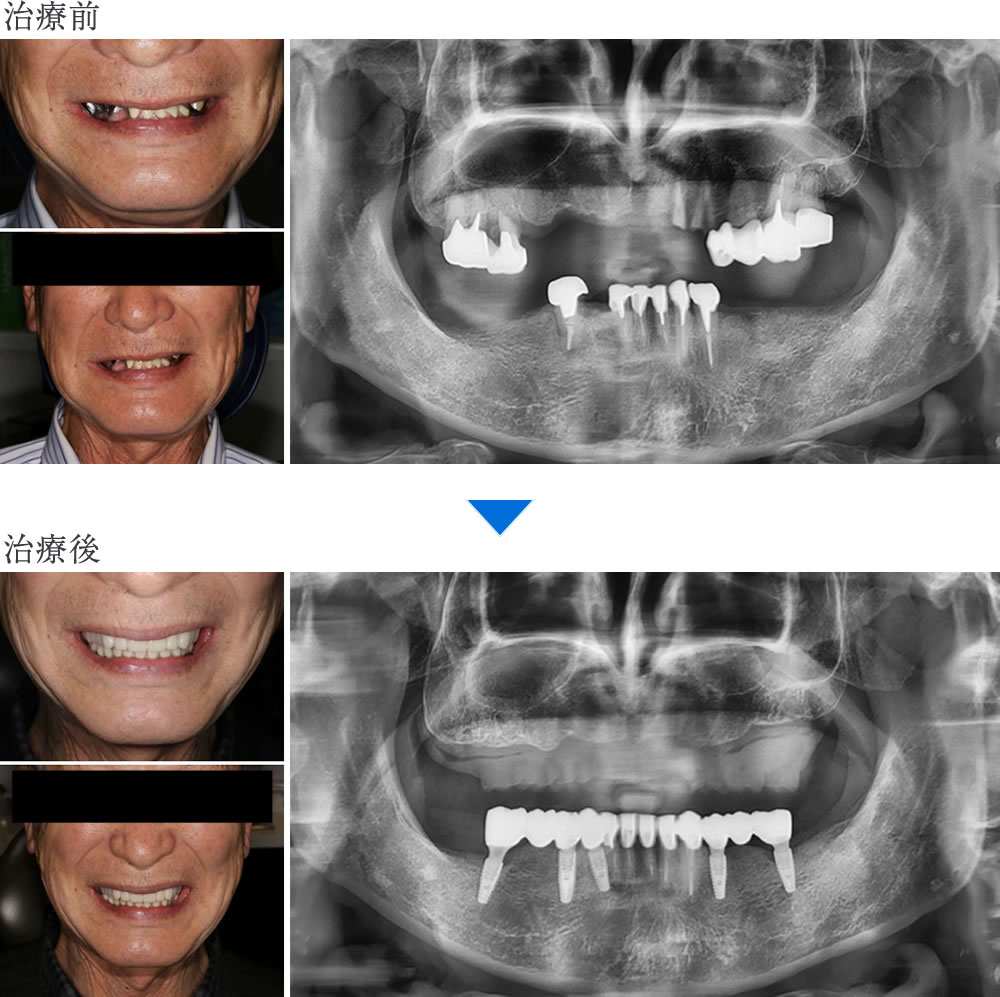

咬合崩壊に対するインプラント・セラミック・義歯による咬合再構成症例

こちらの患者さまは、歯がボロボロで、入れ歯でうまく噛めないという主訴で来院されました。

過去の治療に関しては、痛くなったり、被せ物が取れたりした時に歯医者に行って応急的に治すという事を繰り返していたとの事です。今回は時間をかけてしっかり治療して、ちゃんと噛める状態と見た目も綺麗な状態にしたいというご要望がありました。

初診時の状態

残存している歯は全て不良補綴物の状態で、虫歯も進行していました。多数の欠損が認められ、すれ違い咬合という、上下の歯が噛み合う場所がなく、噛み合わせが非常に不安定な状態でした。

古い入れ歯を入れた状態では、修理を繰り返し、乱れた歯の状態で無理やり噛ませている事がわかります。

欠損も多数あり、口元の審美性は完全に失われた状態でした。

レントゲン検査により、保存不可能な歯が多数認められました。

こちらの患者さまは、ちゃんと噛める状態と見た目も綺麗な状態にしたいというご要望がありました。

このような口腔内の場合、全体的に噛み合わせを再構築しなければならないので、再構築する際に補綴設計の全体バランスが非常に大切になります。

上顎は、挺出してしまい虫歯にもなっている奥歯を全て抜歯し、総入れ歯にすることで、咬合平面を整える事と見た目の改善をする事が可能になると判断しました。

下顎は、不良補綴物が入って虫歯になっている右下4を抜歯した後、前歯5本はセラミッククラウンで治療することで歯の形態を回復し、欠損部の奥歯にインプラント治療を行うことで、患者さまの要望を叶える事ができると考えました。

【治療方針】

・上顎:全て抜歯 → 自費総入れ歯

・下顎:右下4抜歯 → 前歯セラミッククラウン、奥歯インプラント

インプラントの仮歯・下顎前歯のセラミック・上顎に仮の総入れ歯を装着

インプラントの仮歯と下顎前歯のセラミック、上顎に仮の総入れ歯が入った状態です。

最終補綴物の装着

仮歯の状態で問題がないかを確認し、下顎臼歯部インプラントと下顎前歯部セラミッククラウンをセットしました。

治療を終え、口元の審美性が改善している事がわかります。

治療前後の比較

▼口腔内

▼顔貌・レントゲン画像

すべての治療が終了し、「歯がボロボロで入れ歯ではうまく噛めない」という主訴が改善され、「ちゃんと噛める」「見た目も綺麗」な状態になって、ものすごく嬉しいという声を頂きました。

現在では、何でもしっかり噛めるようになり、口元を気にせず笑えるなど、口腔内のストレスなく生活できているとのことです。時間や費用はかかったものの、「思い切って治療を受けて本当に良かった」とのお言葉をいただきました。

| 年齢/性別 | 60代/男性 |

|---|---|

| 治療期間 | 2年11ヵ月 |

| 治療回数 | 20回 |

| 治療費 | 5,080,600円(税込) |

| リスクなど | ・インプラント手術後は内出血をはじめ、まれに唇、舌、頬、歯肉そして歯牙の感覚マヒが一時的に発生する場合があります。 ・処方された薬剤の服用により吐き気、めまい、など一時的な副作用が現れることがあります。 ・部分的に強い力がかかると、つめ物・かぶせ物が破損したり、脱離したりする可能性があります。 |